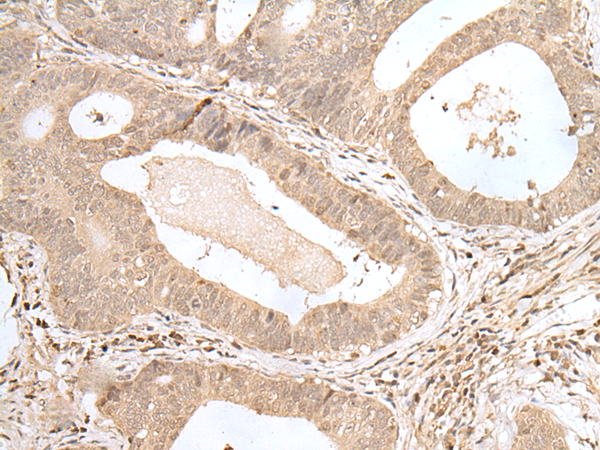

IHC positive control: |

Human gastric cancer and human thyroid cancer |

IHC Recommend dilution: |

25-100 |